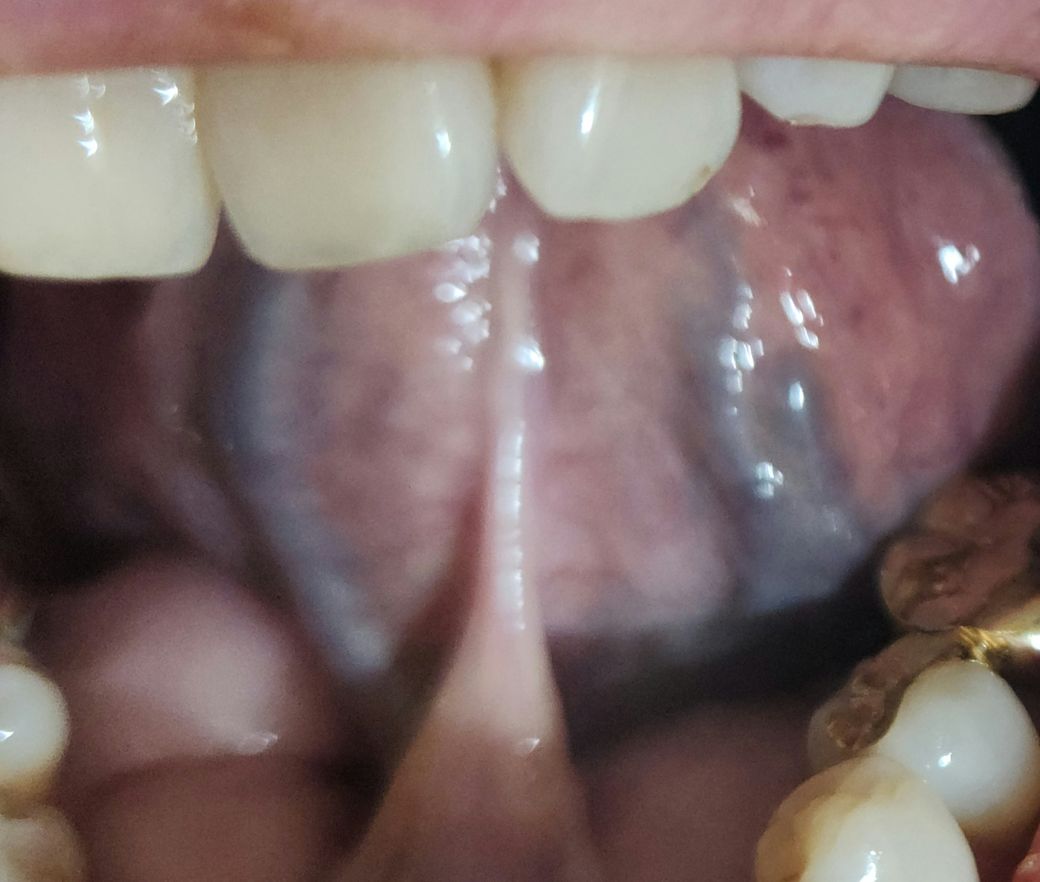

혀밑에 저렇게 보이는데요 구강암일까요?

문득 오늘 보니 혀밑이 양쪽으로 파란색으로 u자모양으로 있는데

겁이나네요 통증이나 다른 이상은 없습니다 ㅠ

혀의 혈관이 비쳐 보이는 것이니 걱정 안해도 됩니다. 혀에는 혈관 분포가 많이 그렇게 보이기도 합니다. 정맥혈관이 보이는 것입니다.

단순 혈관을 말씀하시는 것으로 보이며 구강암과 같은 이상 소견은 관찰되지 않습니다. 어떤 부분이 문제인지 잘 보이지 않습니다.

사진에 보이는건 혀 밑에 잇는 혈관입니다. 다른 사람보다 혈관의 굴기가 많이 굵어서 저렇게 보이는겁니다.

구강 내 혈종의 경우 다양한 가능성을 가지고 있기도 하며 일반 치과에서는 진단하기 어렵습니다. 대학병원 가보시기 바랍니다.